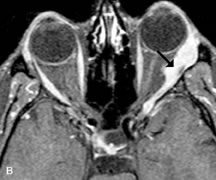

On MRI, uveal melanomas have a typical appearance that helps to differentiate them from other primary and secondary intraocular tumors as well as choroidal detachments. Pigmented melanomas are hyperintense on Tl-weighted images, hypointense on T2-weighted studies, and hyperintense on proton density–weighted examinations (Fig. 24).30,31,50,80–82 These signal characteristics have been attributed to the paramagnetic properties of melanin because of stable free radicals that shorten the T1 and T2 relaxation times. Moderate enhancement is seen on postgadolinium T2-weighted images. Gadolinium-enhanced T1-weighted images are particularly sensitive in detecting choroidal melanomas.83 MRI may be less sensitive in detecting extrascleral extension of tumor than echography performed by an experienced ultrasonographer.84

Fig. 24. A. T1- and (B) T2-weighted MR scans demonstrate a small nodular intraocular mass (arrows) that is very hyperintense on the T1-weighted scan and hypointense on the T2-weighted image. This signal intensity pattern is due to the presence of free radicals within melanin granules. C and D. Postcontrast fat-suppressed T1-weighted scans demonstrate homogeneous intense enhancement of the lesion and no evidence of seleral penetration or optic nerve invasion.